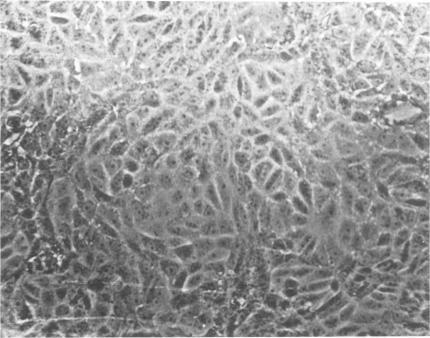

Comparative studies between two measles virus strains isolated from patients with subacute sclerosing panencephalitis (SSPE) and a prototype low tissue culture passage Edmonston measles virus are described. Differences were noted in several properties. The findings described in this report suggest that strains of measles virus associated with SSPE have different biological properties and apparently cannot be distinguished from laboratory and field strains of the virus.

本文描述了从亚急性硬化性全脑炎(SSPE)患者分离出的两株麻疹病毒与一株低组织培养传代的原型埃德蒙斯顿麻疹病毒之间的比较研究。在几个特性方面发现了差异。本报告中描述的研究结果表明,与SSPE相关的麻疹病毒株具有不同的生物学特性,显然无法与该病毒的实验室株和野毒株区分开来。